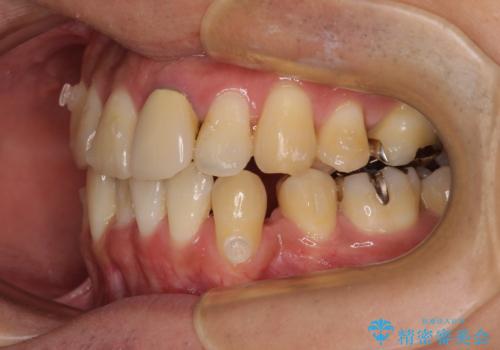

- 下顎の八重歯を気にして来院された患者様です。

左下以外、3本の第一小臼歯が既に抜去されており、左下は八重歯になっている状態でした。

左下の八重歯は手前に傾斜していたため、インビザラインによる抜歯矯正が可能と判断し、後方にある第一小臼歯を抜歯してインビザラインにて矯正治療を行うこととしました。

ワイヤー矯正と比較すると、八重歯が後方に傾斜した仕上がりとなりましたが、患者様ご希望のインビザラインにて十分な歯列を達成することができました。